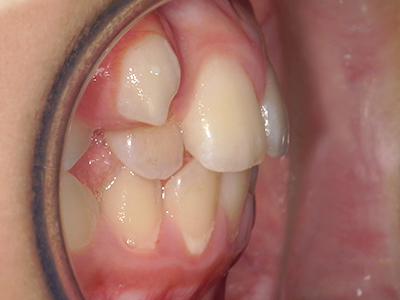

歯並びの相談に来られるお子様は、口呼吸をしているケースが多く、これが歯並びに大きな影響を与えています。

↓ - 頬の圧力が上の歯列にかかりやすくなる

↓ - 上あごが狭くなる

↓ - さまざまな不正咬合が生じる

ないき歯科クリニックでは、上あごの成長不足を補い、鼻呼吸を獲得しつつ歯列を整え、将来のお口をより健康な状態にすることをゴールに定める矯正治療をおこなっています。